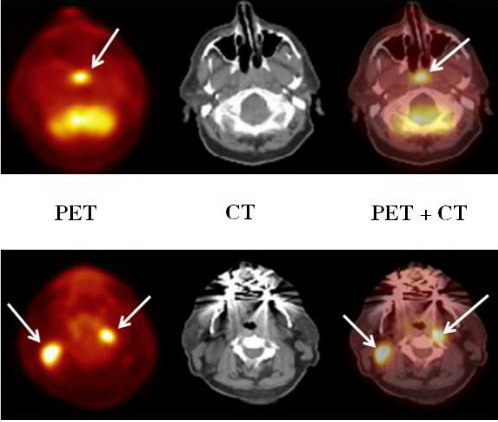

4.2. Ghi hình với PET/CTGhi hình với máy PET/CT là một trong những kỹ thuật ghi hình hiện đại nhất hiện nay. Với cách kết hợp này chúng ta sẽ tận dụng những ưu điểm của CT và của PET.

· Kết hợp máy PET với CT - Scanner tức là ghép 2 loại đầu dò trên một máy và dùng chung hệ thống ghi nhận lưu giữ số liệu và các kỹ thuật của máy tính.

· Do bệnh nhân đồng thời vừa được chụp CT vừa được chụp PET, nên hệ thống này cho phép ghép chồng hình ảnh của CT và xạ hình (PET) lên nhau.

· Sự phối hợp hình ảnh trên đã giúp chẩn đoán bệnh ở giai đoạn rất sớm, chính xác, tăng độ nhạy, độ đặc hiệu của kỹ thuật PET/CT nhờ có được đồng thời hình ảnh cấu trúc gỉai phẫu của CT và hình ảnh chức năng chuyển hoá của PET.

Như vậy ghi hình với PET/CT sẽ cho hình ảnh kết hợp của:

· CT: với hình ảnh cấu trúc gỉai phẫu rõ nét, và đóng vai trò như một khuôn mẫu định dạng các tổ chức giải phẫu chính xác ở vị trị cần nghiên cứu và cần chẩn đoán.

· PET: với hình ảnh chức năng, các tổn thương được phát hiện rất sớm với độ nhạy cao. PET có độ nhạy và độ đặc hiệu cao trong phát hiện tổn thương, đặc biệt trong ung thư.